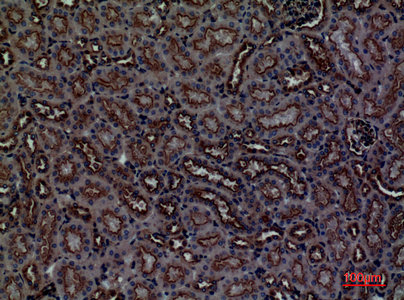

- Scientific DescriptionRabbit polyclonal antibody to CDCP1.